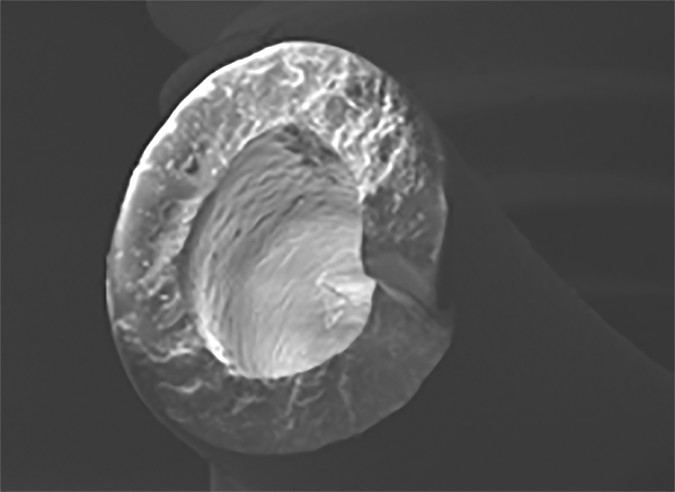

Braun et al. [4] performed a set of experiments investigating the mechanical properties of both de novo and explanted port catheters. They found clear correlation between material properties and clinical performance. Specifically, both native catheters exposed to moderate mechanical stress tests and explanted catheters from cancer patients had a progressive loss of barium sul-fate (BaSO4) particles, which are introduced in almost every catheter material to make it radiopaque. The loss of BaSO4 particles between the silicon bonds essentially leaves microscopic holes in the catheter, leaving areas of increased vulnerability that render the catheter prone to rupture (Fig. 1). Interestingly, more BaSO4-related cracks were observed in silicone than in polyurethane catheters.

A, Overview (×100) of catheter at site of rupture.

B, Magnification of rupture site (×232) shows additional surface defect in close proximity to rupture site.

C, Magnification of same catheter more distant from rupture site (×515) shows multiple surface defects.

D, Further magnification (×1290) shows hole in catheter after release of BaSO4 particles.